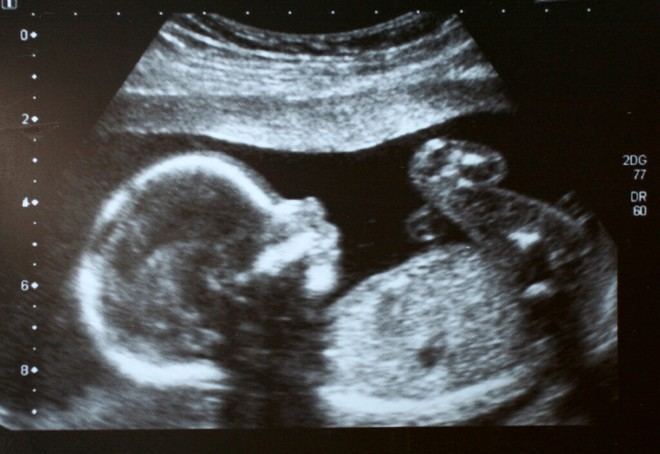

Aproximadamente la mitad de los mortinatos están relacionados con el retraso del crecimiento fetal (FGR), una condición provocada por un funcionamiento inadecuado de la placenta que limita el crecimiento del bebé. Actualmente, las herramientas ecográficas solo logran detectar alrededor del 50% de los casos de FGR, y aunque se identifiquen, no existe tratamiento disponible. Los clínicos deben tomar decisiones complejas sobre el momento del parto, equilibrando los riesgos asociados con un nacimiento prematuro frente al peligro que representa esperar demasiado tiempo.

El profesor Alex Heazell, de la Universidad de Manchester, comentó: “La toma de decisiones clínicas actual depende de indicadores indirectos como el ultrasonido Doppler, los movimientos fetales y los patrones cardíacos. Aunque el Doppler arterial umbilical ha contribuido a reducir el riesgo de mortinato en bebés prematuros, la mayoría de los mortinatos ocurren en embarazos donde los resultados Doppler parecen normales. Es crucial destacar que ningún test clínico existente puede evaluar directamente la oxigenación fetal, que es el principal factor determinante del riesgo de mortinato.”